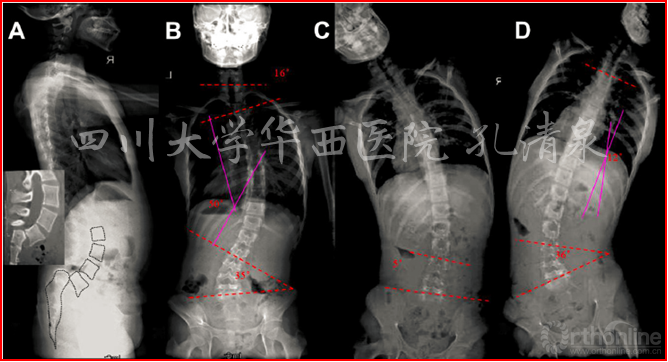

图1 术前X线示:腰5椎IV度滑脱并脊柱侧凸,颈胸弯中立位16°,减轻位0°,胸弯中立位50°,减轻位12°,腰弯33°,减轻位5°,均为非结构性弯。

如果基于上述理论,我们的第一例病例应该接受腰椎滑脱和侧凸的同期手术。但我们经过深入分析,腰椎滑脱是有症状的,具有手术指针,脊柱侧凸虽然角度较大(颈7-胸3侧凸Cobb角16°,胸3-腰2侧凸Cobb角50°,腰3-腰5侧凸Cobb角35°),但其柔韧性较好(减轻位上胸椎侧凸12°腰椎侧凸5°),并且没有影像学上椎体旋转的证据.所以我们认为,这是一种非结构的继发性侧凸的可能性大,其处理不能等同于特发性脊柱侧凸,所以应该尽量减少固定融合节段,动态观察其自发侧凸矫正的潜能。